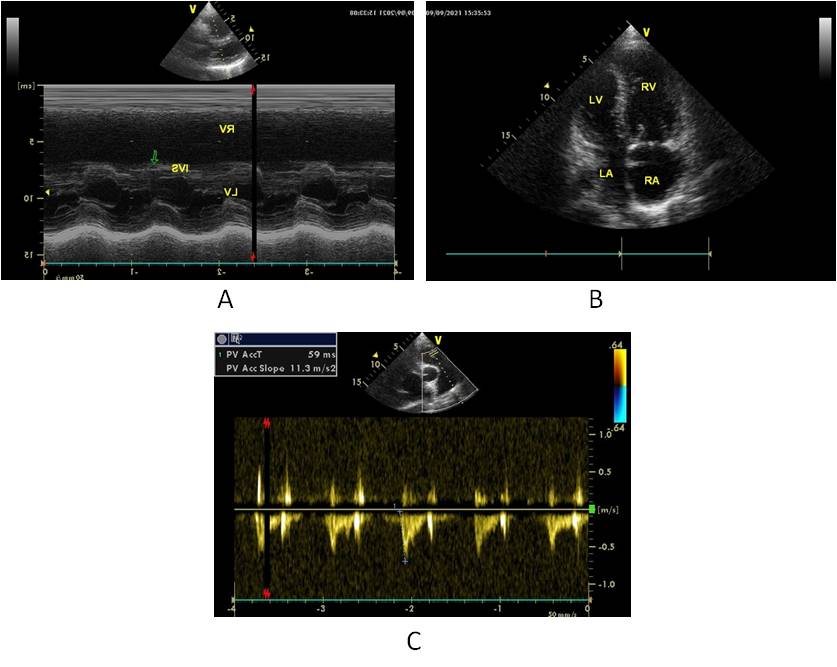

Transthoracic echocardiography (6 September 2021): a sharp dilatation of the right chambers of the heart. Severe pulmonary hypertension, expansion of the PA. Paradoxical movement of the interventricular septum (Figure 3A), the left parts of the heart are compressed by dilated right chambers (Figure 3B). Left atrium 45 х 32 mm, RA 63 х 56 mm. The right ventricle end-diastolic size is 44 mm, left ventricle end-diastolic size — 38 mm. Left atrium: dilated up to 36 mm, with an obstructive type of blood flow. Regurgitation on the left atrium valve of the 2nd degree. Systolic pressure in РA 88 mmHg.

Fig. 3. Parameters of transthoracic echocardiography: Paradoxical movement of the interventricular septum (3А); Sharp expansion of the right chambers of the heart (3В); High rates of peak and moderate pulmonary hypertension (3С).